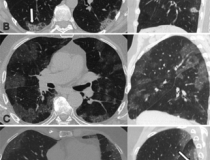

This photo gallery shows the variety of radiological presentations of COVID-19 (SARS-CoV-2) in medical imaging, including computed tomography (CT), radiograph X-rays, ultrasound, echocardiograms and magnetic resonance imaging (MRI). The radiology images show examples of typical COVID pneumonia in the lungs and the numerous complications the virus causes in the body in multiple organs, including the brain, kidneys, heart, abdomen and vascular system.

Ultrasound, especially hand-held ultrasound imaging devices, have become a primary imaging modality for novel coronavirus because of the ease to bag the device and sterilize it after use. CT and mobile X-ray systems are also used as front-line imaging systems for COVID-positive or suspected COVID patients.